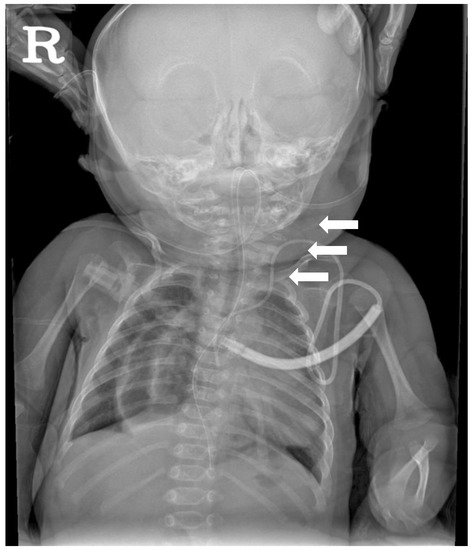

2.3. Diagnostic Assessment